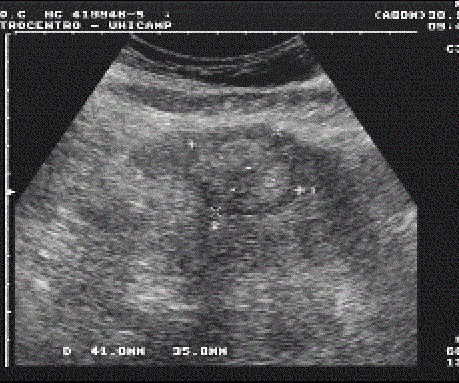

Image echographique du metastase hepatique :

Aspect est variable , souvent multiple a des nodules hypo ,

isoechogene avec contour de hypoechogene , parfoie est

hyperechogene

Image echographique de

metastase du foie : Aspect lesionaire est multiple

en nodulaire iso echogen avec contour

hypoechogen ( Bull's eye sign) |

Signe de "Bull

eye sign" des metastases du foie . Image

echographique du foie |